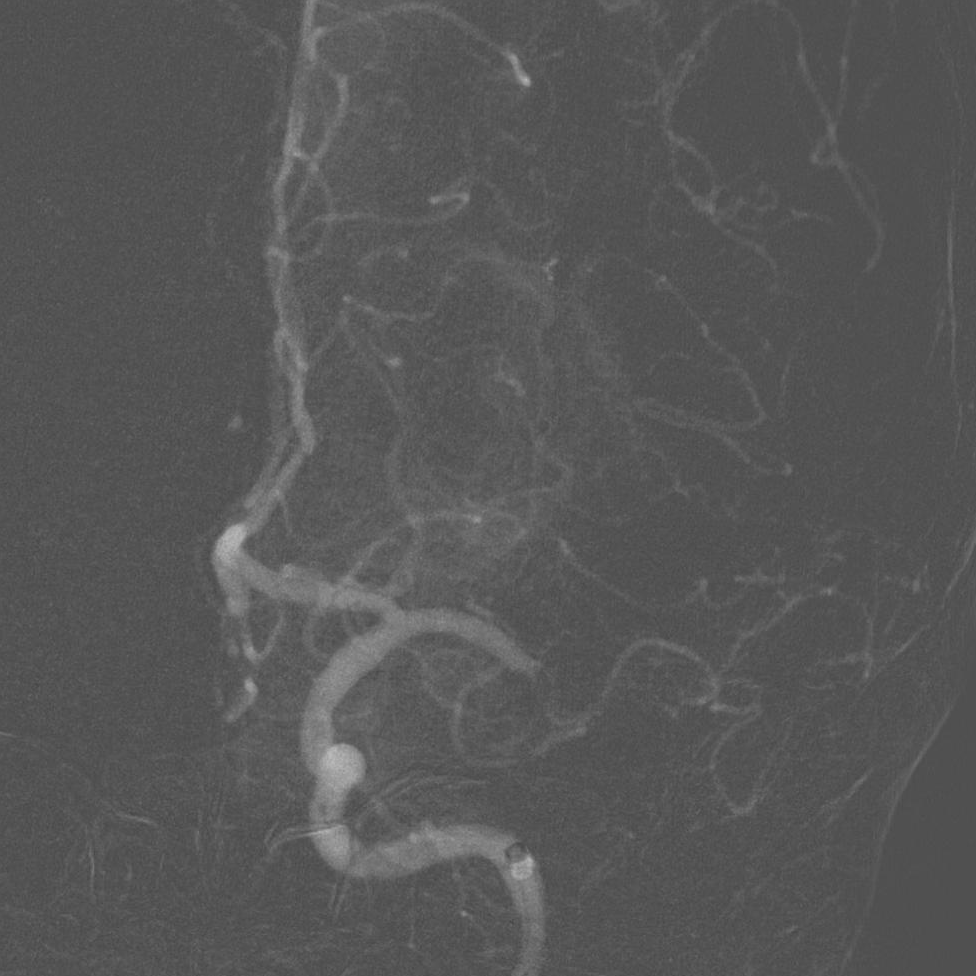

4*20mm Trevo ProVue取栓支架释放,5分钟后抽拉结合取栓,一次取栓,大脑中动脉完全再通。

大脑中动脉完全再通。